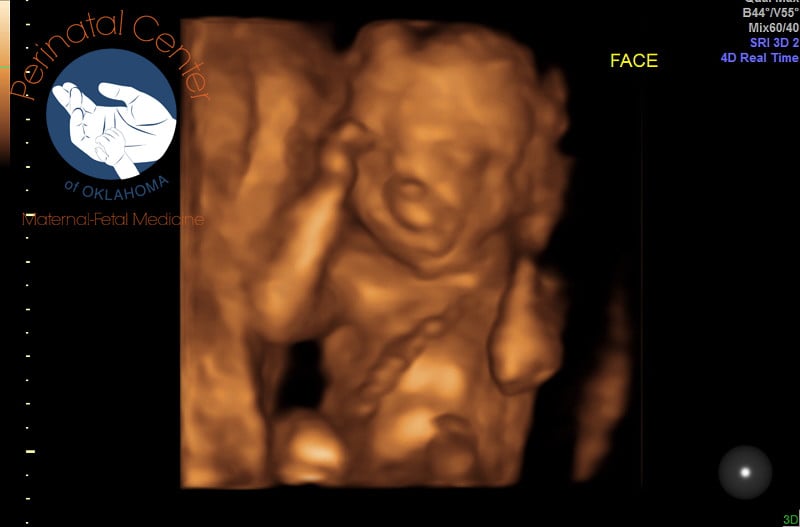

3D/4D ultrasounds- ugh. No way Jose. I feel like they make your baby look like an alien. I'll stick with the traditional... But @DrillSergeantCat your bear cub is adorable!

• @DrillSergeantCat AMEN! We got this image from our tech and her response was "look how cute baby is already!" And my reply was, ".....where is their nose? Baby looks alien like

@Achae - 3D/4D ultrasounds freak me out too. Since I was pregnant with my 2 year old DS, I've been told multiple times that I should have a 3D done because it makes the baby more "realistic" and I'm thinking (as I'm looking at others 3D) is that nope, 3D's make the baby look like an alien or some sort of creature it shouldn't be. @DrillSergeantCat - your lil bear is adorable, but I've seen some that would give me nightmares.

Lilypie Pregnancy tickers

I used to think 3D ultrasounds were strange, especially since I never had one done during my first pregnancy. I went in today for a recheck on my A/S since baby wasn't cooperative the first time around and the tech switched between regular and 3D a couple of times. It was really neat to see the details and I think our picture came out somewhat looking like a baby at 21w3d (but maybe I'm biased). ;)